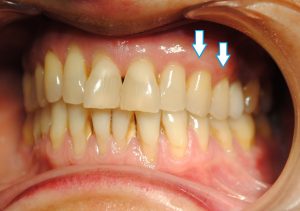

Ejecutados los tratamientos en la parte superior izquierda de la boca (es la parte por la que se ha empezado el tratamiento), este es el aspecto de esta parte de la boca tras el implante y la cirugía mucogingival que solucionó la recesión de encía dotándola de nuevo volumen: